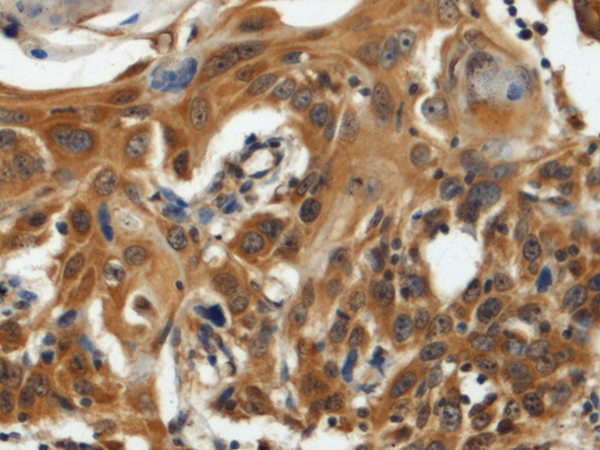

IHC positive control:

Human esophagus cancer and Human tonsil

IHC Recommend dilution:

100-300